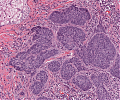

A69 Tubuläres Adenom (Kolon)

Nebeneinander normaler Kolondrüsen und adenomatöser Drüsen.

A69 Tubuläres Adenom (Kolon)

Tubuläre Drüsenbildung mit geringen Epithelatypien und einzelnen noch erhaltenen Becherzellen.

Tubuläres Adenom.png

Tubuläres Adenom des Kolon (Übersicht)

-

Tubuläres Adenom1.png

Tubuläres Adenom mit abruptem Übergang von normaler Darmschleimhaut zum Adenom

-

Tubuläres Adenom2.png

Erkennbar sind Epitheldysplasien mit Ausbildung atypischer villöser Drüsen